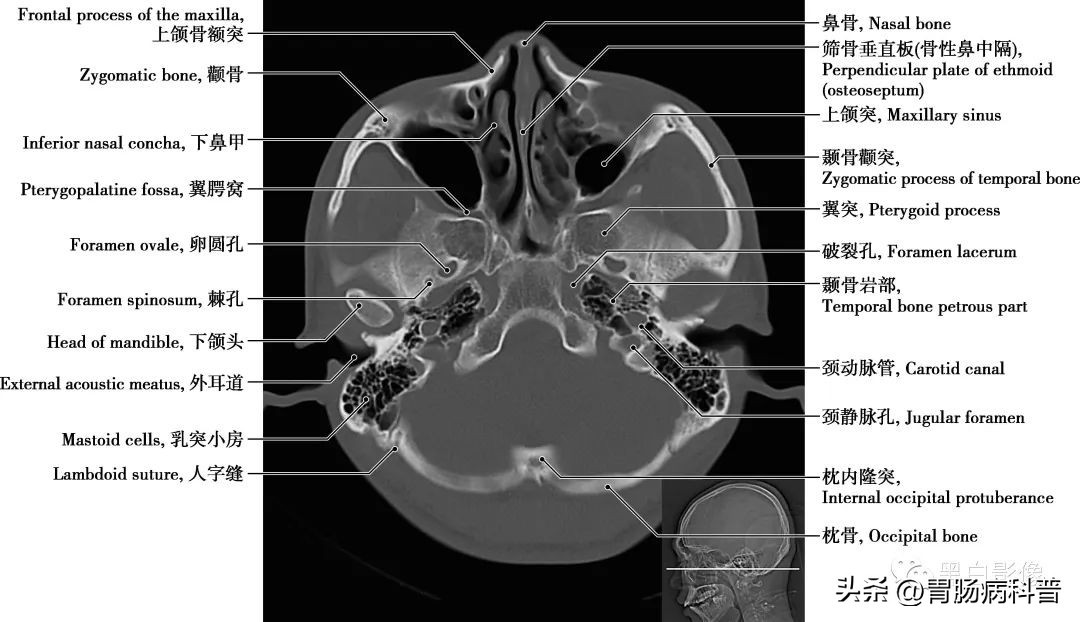

图1-2-18 经下颌头轴位切面

卵圆孔和棘孔 在蝶骨大翼近根部处由前向后可见圆孔、卵圆孔和棘孔,圆孔内走行上颌神经,卵圆孔内走行下颌神经,棘孔内走行脑膜中动脉。颈动脉管 是颈内动脉进入颅腔的管道,在颞骨岩部内弯曲形成一定角度,再经颈动脉管内口于破孔处离开颈动脉管进入颅内